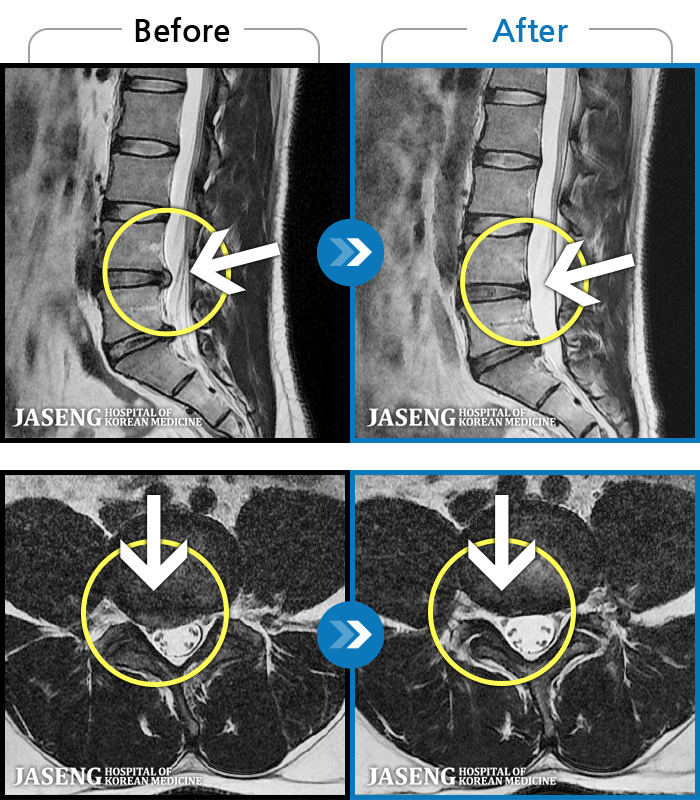

1,240 MRI ũ ʸ Ȯϼ.

| [뱸] 19.11.28~25.05.06